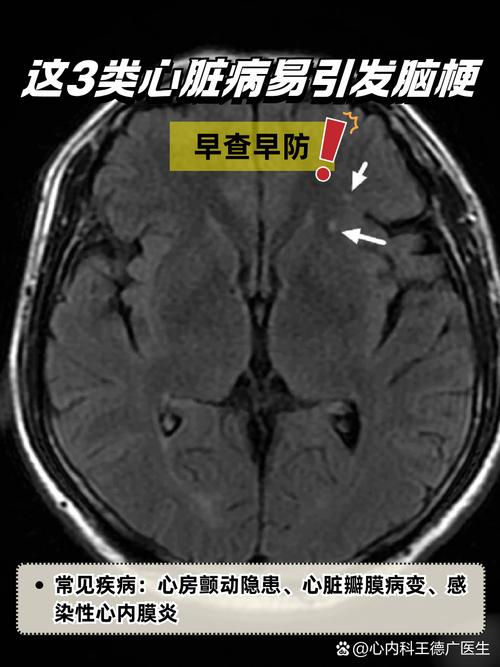

- 头颅CT:首选检查,可以快速排除脑出血,但在早期脑梗可能显示不明显。

- 头颅MRI + DWI序列:对早期脑梗的敏感性极高,可以清晰地显示梗死的部位和范围。